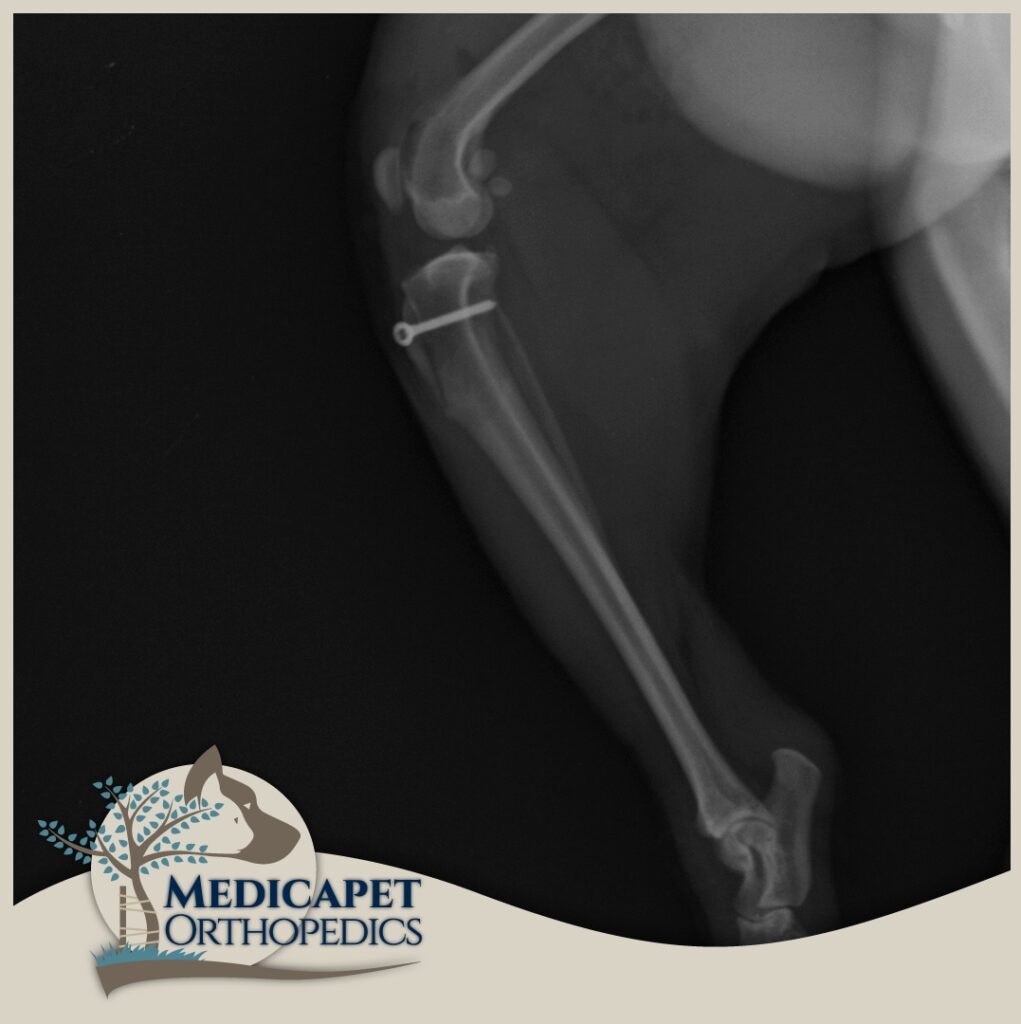

Tuberositas Tibianın Transpozisyonu (TTT)

Patella, patellar ligament aracılığıyla Tibia’nın Tuberositas Tibia adı verilen parçasına bağlıdır. Pek çok luksasyon olgusu bu parçanın dışa doğru eğiminden kaynaklanır. Yapılacak bir osteotomi ile pozisyonu değiştirilen bu parça patellayı dengeli bir pozisyona getirecek şekilde yeniden konumlandırılarak yeni bölgesine sabitlenir. Femur ve Tibia kemiklerinde aşırı eğrilik olmayan hastalarda çok etkili ve yeterli bir uygulamadır.